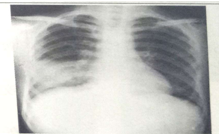

试题1:男性,26岁,受凉后寒颤高热,咳嗽,咳铁锈色痰5天(2分)

A.肺癌

B.气胸

C.正常胸片

D.肺炎

E.胸腔积液

答案:D